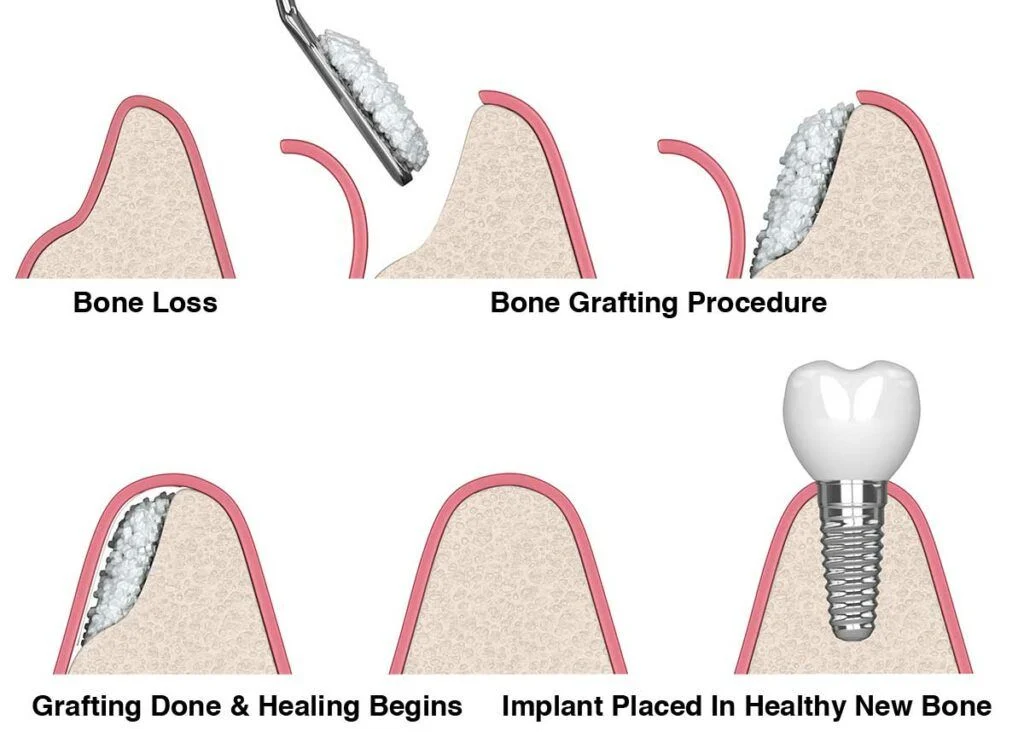

Strengthen Your Foundation for Lasting Implants

Bone grafting is a crucial procedure for patients who have insufficient bone density or volume in their jawbone to support dental implants. This process involves transplanting bone material to build up the jawbone, ensuring a stable and durable foundation for implant placement.

Benefits:

Strengthen Your Foundation for Lasting Implants

Bone grafting is a crucial procedure for patients who have insufficient bone density or volume in their jawbone to support dental implants. This process involves transplanting bone material to build up the jawbone, ensuring a stable and durable foundation for implant placement.

Benefits: